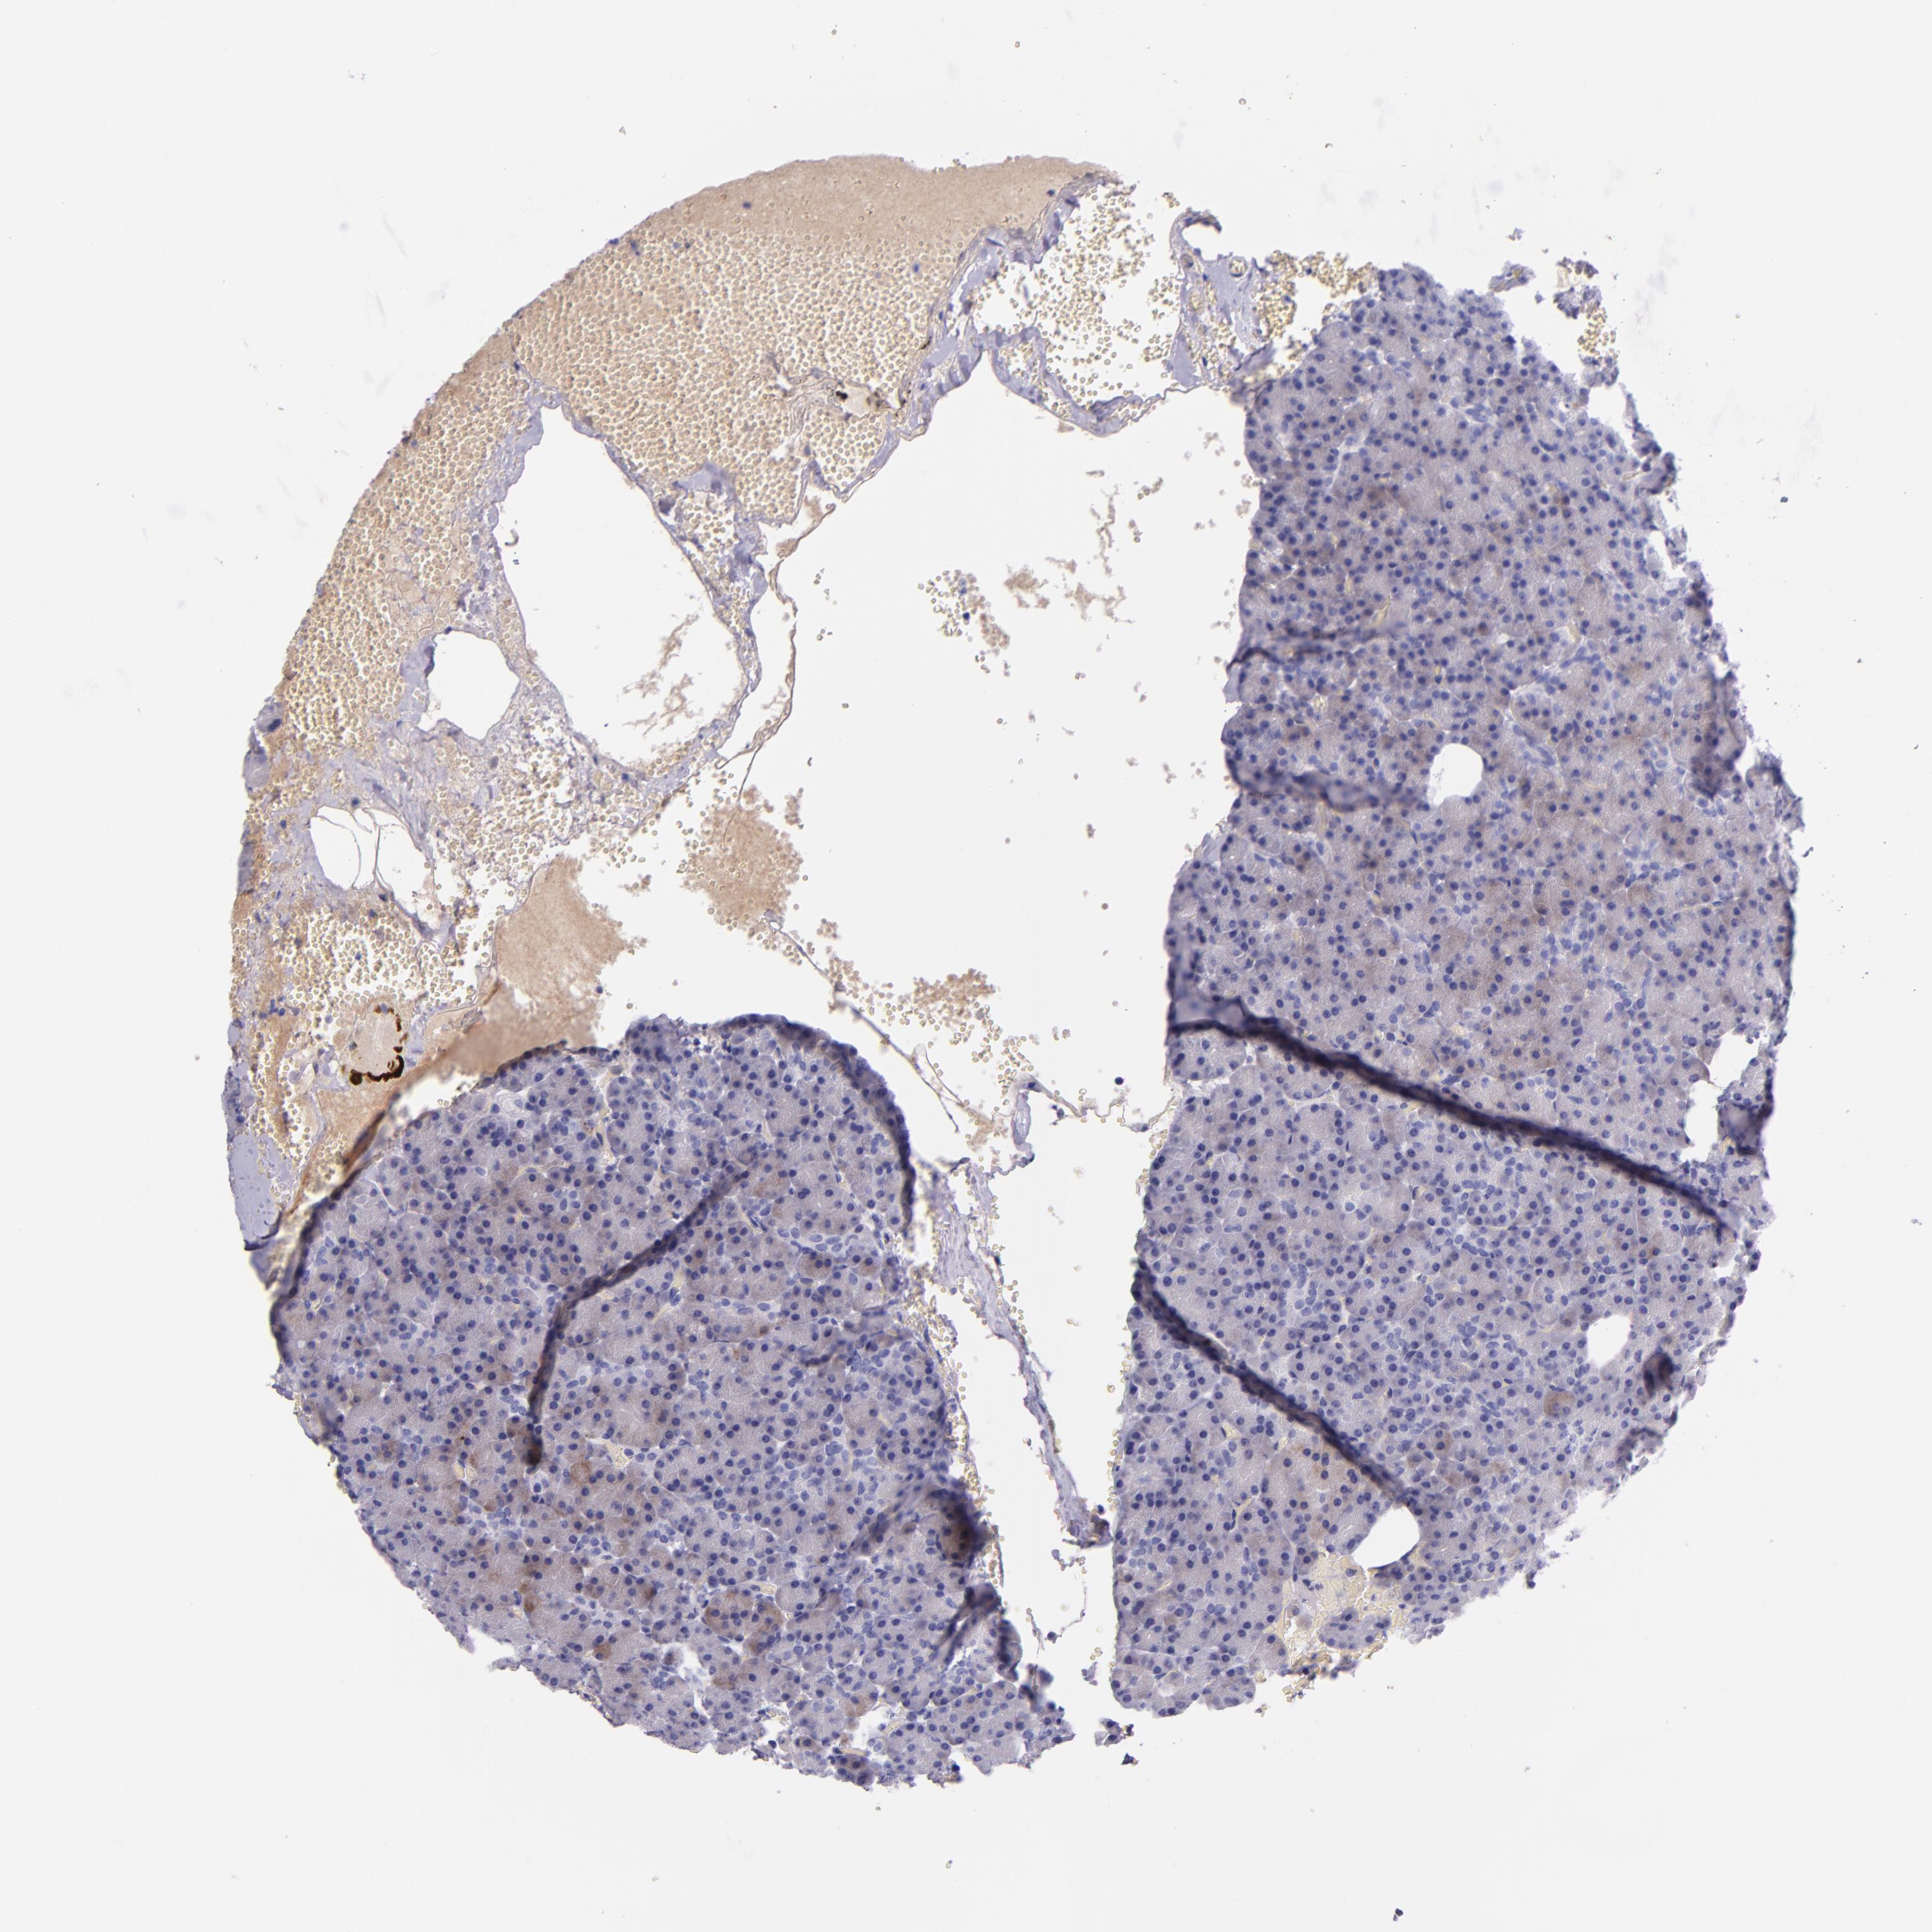

PANCREAS - Antibody stainingi

Antibody staining in the annotated cell types in the current human tissue is reported as not detected, low, medium, or high, based on conventional immunohistochemistry profiling in selected tissues. This score is based on the combination of the staining intensity and fraction of stained cells.

Each image is clickable and will lead to virtual microscopy that enables deeper exploration of all samples and also displays staining intensity scores, fraction scores and subcellular localization as well as patient and tissue information for each sample.

Antibody HPA001616Antibody HPA001645Antibody CAB009809

Exocrine glandular cells Not detectedNot detectedNot detected

Pancreatic endocrine cells Not detectedNot detectedNot detected